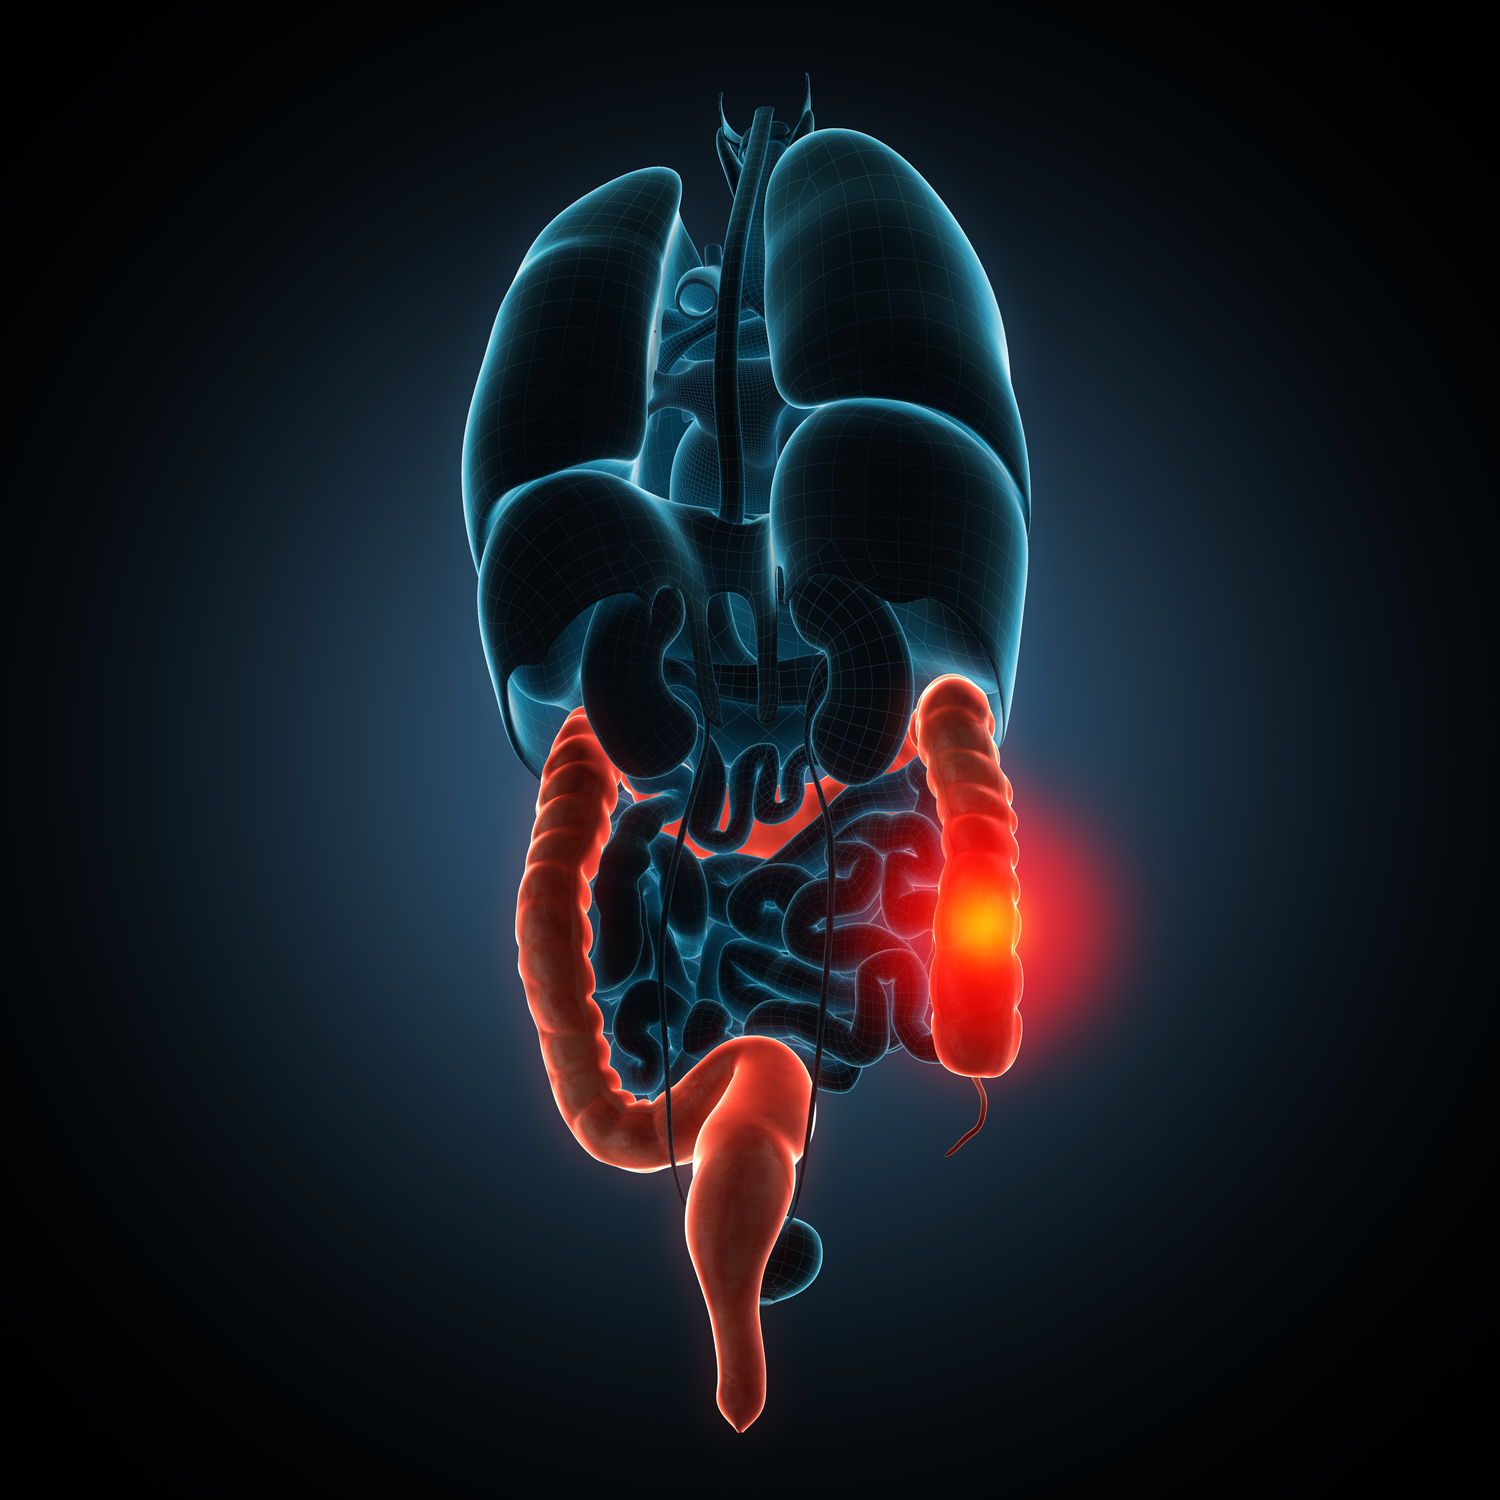

Crohn’s Disease Common Signs and Symptoms

Crohn’s disease is a chronic inflammatory bowel disease that results in the inflammation of the gastrointestinal (GI) tract, which extends from the mouth to the anus. The disease can affect any part of the GI tract. A combination of hereditary, immune, and environmental factors results in the development of this chronic inflammatory disorder. The ileum or small intestine, which goes on to join the large intestine, is affected by signs and symptoms of Crohn’s disease.

Complications of Crohn’s disease:

- Inflammation of the colon: This can also lead to an increased risk of colon cancer, which is why these symptoms should never be taken lightly.